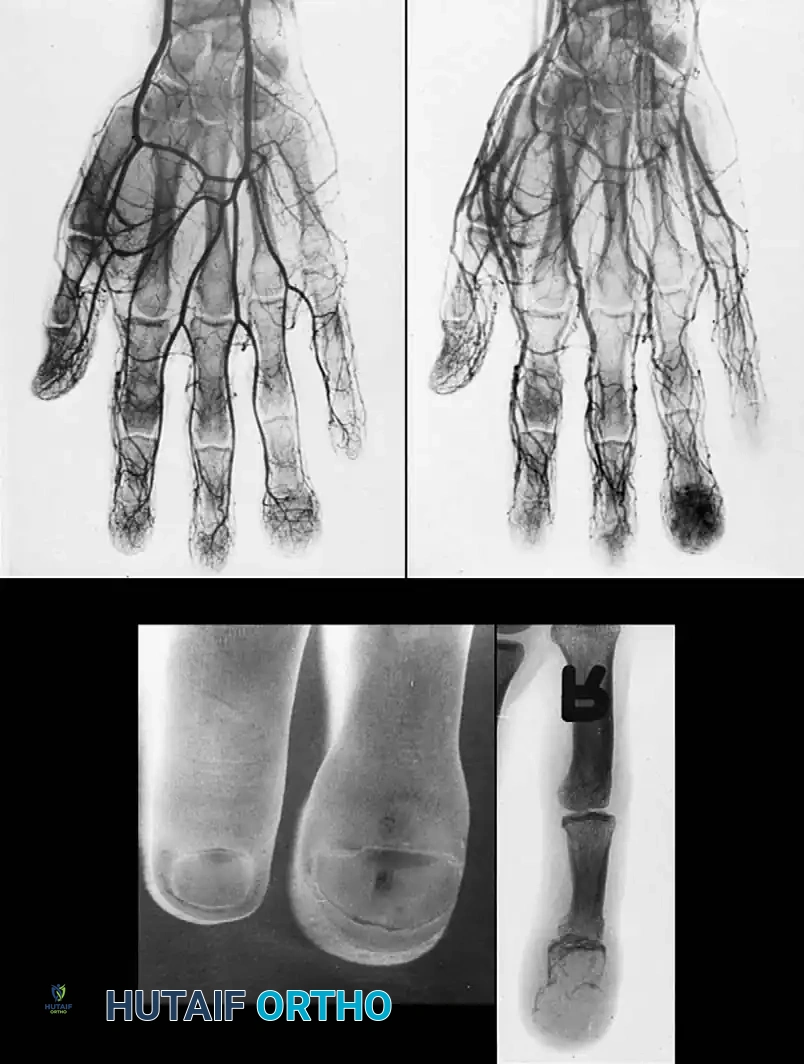

Surgical Excision and Recurrence

Excision is notoriously difficult. These tumors frequently wind in and around the flexor tendons, their synovial sheaths, digital nerves, and occasionally the extensor mechanism, sometimes encompassing three-fourths of

Associated Surgical & Radiographic Imaging